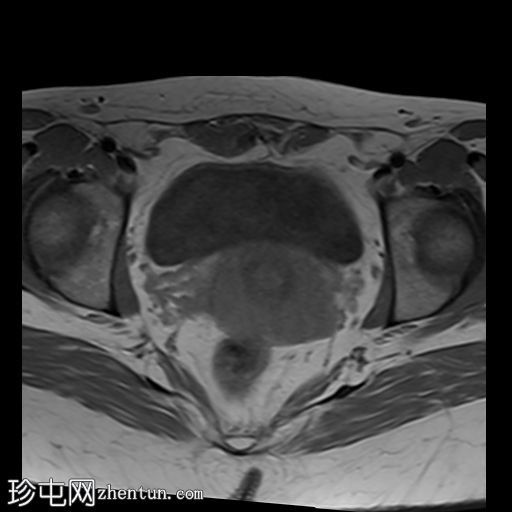

轴位

T2加权像

MRI特征符合剖宫产术后瘢痕子宫内膜异位症,表现为特征性T1高信号伴T1FS持续存在,T2低信号伴内部高信号灶,病灶边缘浸润于腹前壁肌肉内,以及对比增强。

该病灶累及腹白线并浸润腹直肌,主要位于中线左侧,耻骨联合及结节处腹直肌起点上方。

影像学表现符合病灶内出血成分,提示既往剖宫产瘢痕处存在异位子宫内膜组织。

双侧卵巢增大,内含多个小卵泡(每侧卵巢10-12个或更多)。